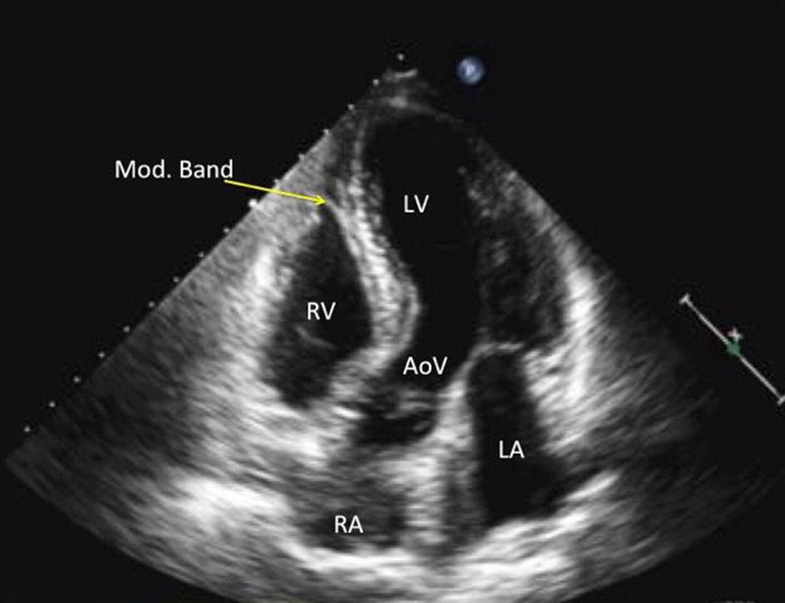

What view is this?

5 chamber view (used to recored aortic root, outflow, LVOT)

Crisscross view